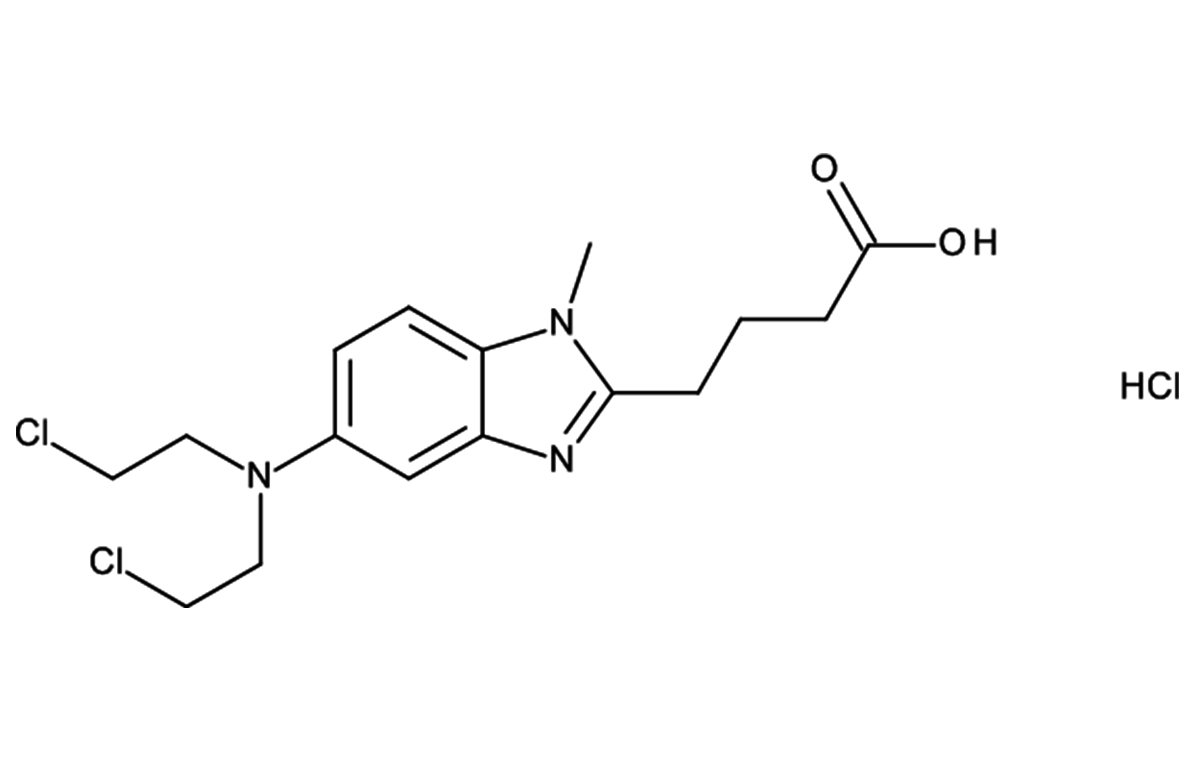

- Leading manufacturer of key anti-cancer APIs.

- One of the emerging API manufacturers in the India.

- Major supplier to leading generic companies in India and ROW markets.